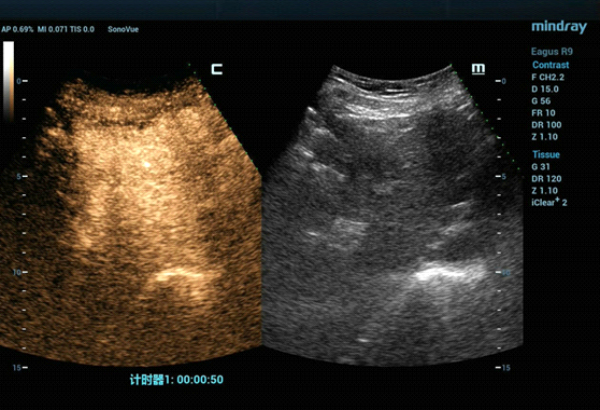

??? ??? ?? ????? ???(MWA)? ?? ?????? ?? ?????? ??? ???? ??? ?? Contrast-enhanced CT? ???? ??? ?? ??? ??? ?? ??? ?? ??? ????? ???? ???? ????? ??(MWA)? ??? ???????.

??? ????? ??? 2D ??? ??? ???? ???? ???? ??? ? ????? ??? ??? ?? ?????? ???? ?? ??? ???? ???? ??? ? ?????. ??? ??? ???? ??? ?? CT ??? ??? ???? ??? ??? ??? ?? MWA? ?? ???? ??? ???? ?????. CEUS(Contrast-Enhanced Ultra Sound)? ???? ?? ? ??? ??? ????, ?? ? ?? ??? ???? ?? ?? ??? ???????.?

?? ??? ??? CEUS(Contrast-Enhanced Ultra Sound)? ???? ????? ??? ??? ??? ???? ??? ? ??, ????? ???? ???? ????, ?? ??? ?????? ??? ? ????. ??? ??? ??? ???? ??? ?? ????? ??(Ultrasound-guided MWA)? ???? ?? ??? ?????.